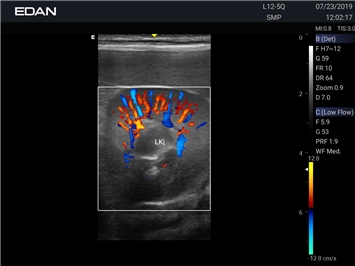

Энергетический допплер:

Да

Цветовой допплер:

Постоянно-волновой допплер:

Импульсно-волновой допплер: